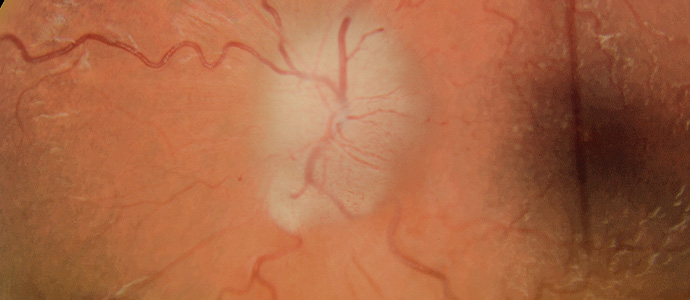

중심망막동맥폐쇄

망막에 혈액을 공급하는 중심 동맥이 막히는 응급 질환으로,

혈류가 끊기면 망막 세포가 빠르게 손상되어

짧은 시간 안에 시력이 급격히 떨어질 수 있습니다.

수 시간 내에 치료가 이루어지지 않으면

영구적인 시력 손실로 이어질 수 있습니다.